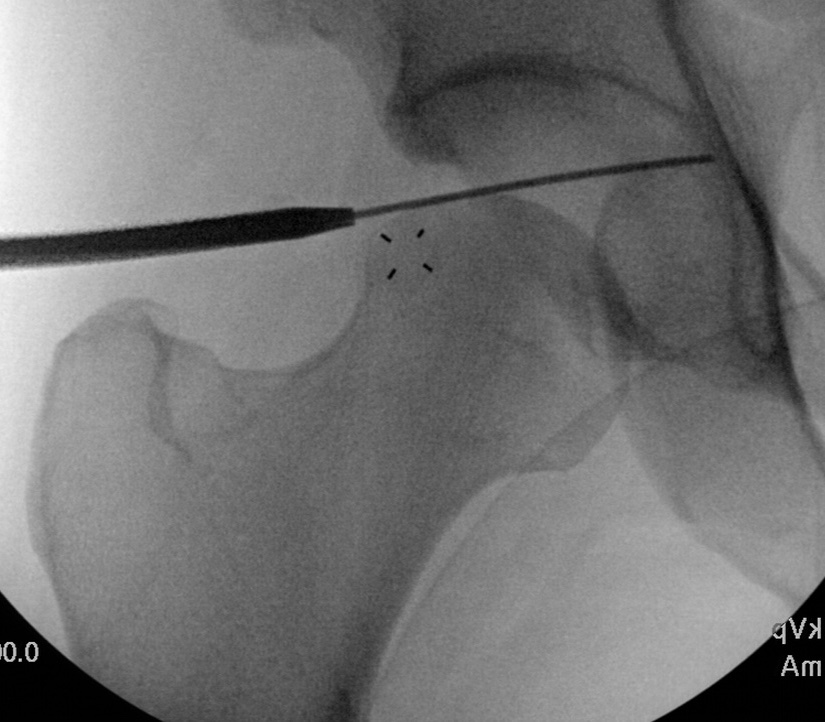

Mid Anterior portal

- stay lateral to line drawn down from ASIS to prevent NV injury

- aim for tip of camera on image intensifier

- judge anterior posterior using femoral head / acetabulum

- enter capsule between labrum and femoral head